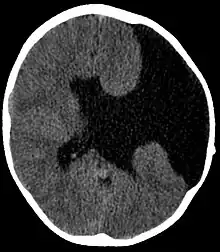

| Axial CT scan showing schizencephaly in a 6-year-old child | |

Schizencephaly (from Greek skhizein 'to split' and enkephalos 'brain')[1][2] is a rare birth defect of the brain, characterized by abnormal clefts lined with grey matter that form the ependyma of the cerebral ventricles to the pia mater. These clefts can occur bilaterally or unilaterally. Common clinical features of this malformation include epilepsy, motor deficits, and psychomotor retardation.[3]